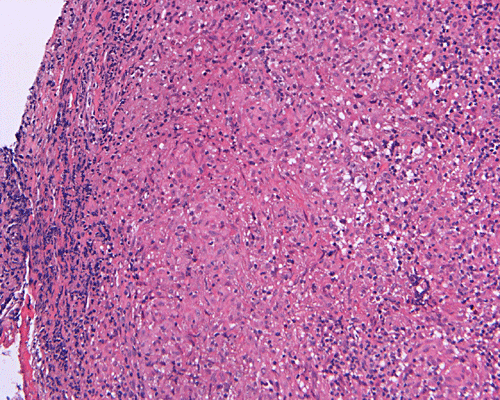

Paraffin sections: The entire volume of the tissue is made up of a granulomatous inflammation with poorly formed granuloma (Panel F, G, and H). The density of the lymphocytes is variable in different areas. In some areas, there is a rather intense lymphocytic infiltration accompanied by scant atypical cells with enlarged nulcei and prominent nucleoli (arrows in Panel I and J, Panel J is a higher magnification of Panel I). These atypical cells are quite easy to be missed. No microorganisms were identified by acid fast stain, PAS stain or GMS stain. The lymphocytes but not the atypical cells are positive for CD20 (Panel K) or CD3 (Panel L). The granulomatous background is strongly positive for CD68 (Panel M). Only rather faint positive staining for placental alkaline phosphatase (PLAP) is demonstrated and the interpretation is difficult as they are present in areas with crush artifact (Panel N). Many of the large, atypical cells are positive for CD117 (c-kit) (Panel O).

Intracranial germinoma is histologically identical to ovarian dysgerminoma and testicular seminoma. There is a tendency to infiltrate adjacent structures and to spread throughout the ependyma, the ventricular system and subarachnoid spaces. Microscopically, they consist of nests, lobules, cords, and/or sheets of large round tumor cells with well-defined borders, clear to pale cytoplasm with artifactual vacuolization, round and centrally located nuclei with open chromatin and prominent round or bar-shaped nucleoli. The cytoplasm is glycogen-rich, making these cells periodic acid-Schiff (PAS)–positive and diastase sensitive. These tumor cells are mitotically active. Atypical mitosis, however, is not a common finding. Necrosis is usually not prominent.  In the most classic histologic picture, clusters and cords of large germinoma cells are separated by a dense, lymphocytic infiltration admixed with some macrophages and a delicate fibrovascular network. Plasma cells may be found. At medium-power magnification with hematoxylin and eosin stain, the contrast between the smaller, darkly staining lymphocytes and the larger, pale staining cytoplasm of neoplastic cells is virtually pathognomonic. The amount of inflammatory cells can have wide variations among different tumors. In some occasions, the large germinoma cells are difficult to be found and the overall picture may suggest a lymphoma. Syncytiotrophoblastic cells can also be present. These cells should not be mistaken as evidence of choriocarcarcinoma.

Germinomas can elicit an atypical gliosis in the surrounding glial tissue which may be confused with malignant glial neoplasms. This is true particularly of specimens taken from the periphery of the germinoma. The tumor may appear as a desmoplastic tumor. The inflammatory response may be problematic in reaching a histologic diagnosis, especially in small biopsies, as macrophages can be difficult to distinguish from a non-seminomatous neoplastic component.

Granulomatous changes are common findings in germinomas and intracranial germinomas follow this general trend 3, 4, 5. It can be extensive. This feature is particularly problematic in neuropathologic when stereotactic biopsy is performed and the amount of tissue available for examination is limited as illustrated in this case. During intraoperative consultations, a frozen section diagnosis of granulomatous inflammation should prompt additional sampling as isolated granulomatous inflammation of infectious origin and sarcodosis are quite uncommon in the pineal gland.